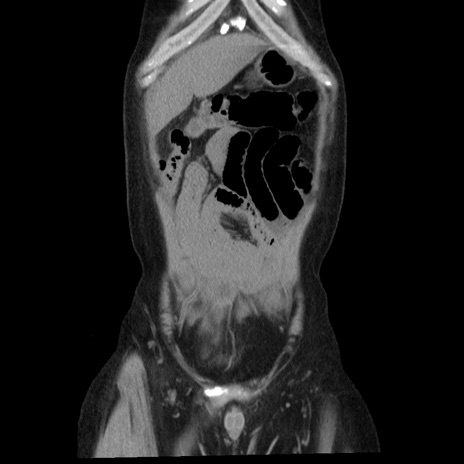

症例29(冠状断像)

【症例】40歳代男性

【現病歴】2日前から胃痛あり。徐々に周期的な激痛に変化した。本日になっても激痛があるため受診。

【身体所見】意識清明、BT 38-39℃台あり、腹部:膨満、やや硬、右下腹部に圧痛あり。

【データ】WBC 8500、CRP 23.26